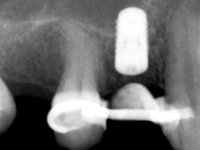

A CT scan was performed to evaluate the available bone heritage and to choose the type and size of implant to be placed. An impression of both jaws was made in alginate, as well as intermaxillary recording for laboratory work on a provisional prosthesis. The provisional prosthesis was made by including a metal wire in a prosthetic tooth adapted to the edentulous space. The root was carefully removed and the implant was placed in the tooth socket corresponding to tooth 1.4. The remaining space between the walls of the alveolus and the implant was filled with regenerative material and then sutured. The prosthesis was previously adapted to the postoperative zone and was then bonded to adjacent teeth. Teflon was used to promote the best possible insulation. Bonding was done using photopolymerizable composite resin using the palatine and inter-proximal walls of the adjacent teeth. After 10 days, the suture was removed and one month later osseointegration was confirmed. Exposure of the implant and placement of the healing screw was performed after 10 weeks. The cervical portion of the provisional tooth had to be reduced to accommodate the healing screw. Stabilized peri-implant soft tissues were impressed using open tray technique with soft and regular consistency putty silicon. In the laboratory the work model was made, along with the choice of pre-fabricated components for the confection of a metal-ceramic crown screwed to the implant with the brand’s interface. Removal of the provisional bridge was done with great care not to touch the interproximal surfaces of the teeth adjacent to the edentulous space. The crown was screwed to the implant, and after imaging, the seating was given the final tightening with 35N of torque. The screw access hole was filled with Teflon and closed with composite resin. The patient manifested satisfaction with the aesthetic and functional rehabilitation achieved.